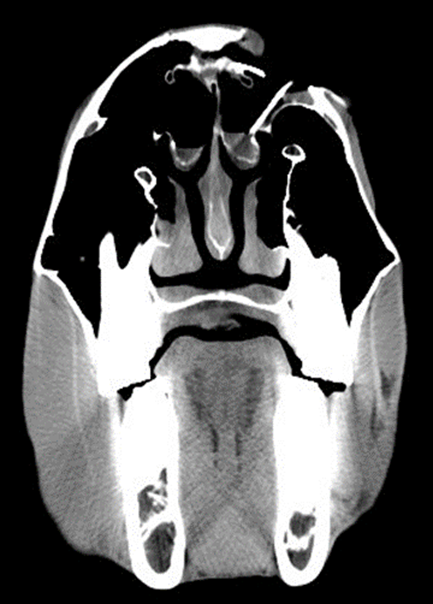

The equine skull is complex and composed of bones including the incisive bone, nasal bone, frontal bone, maxilla, lacrimal bone, zygomatic bone, interparietal bone, parietal bone, temporal bone, sphenoid bone, occipital bone, ethmoid bone, palatine bone, vomer, pterygoid bone, and mandible.4 The most common bones injured in skull fractures are the nasal, frontal, and maxillary bones with the zygomatic process of the frontal bone.5 Additionally, lacerations to the face and subsequent facial bone fractures can be complex and involve various structures such as sinus compartments, the lacrimal duct, orbit, and cerebrum (Figure 1a and Figure 1b).

As they are frequently traumatic in origin, these fractures are often open, displaced, and comminuted with numerous fragments of various sizes. Clinical signs will vary according to the extent of the trauma and can often include multiple lacerations ranging from small abrasions to large, full thickness wounds, nasal epistaxis, emphysema, stertorous breathing, and crepitus. Associated skull fractures should be examined thoroughly to obtain a comprehensive and complete evaluation of the extent of the damages. In addition to a general physical examination, a comprehensive examination including ocular, oral, and neurological evaluations (cranial nerves) should be undertaken.4 Further diagnostics such as an upper airway endoscopy, radiographs, ultrasound, and CT images will often help characterize the full extent of the trauma.6-8